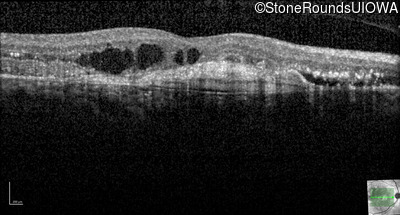

Optical Coherence Tomography - Right - 20/250

Exemplar / OCT Stack